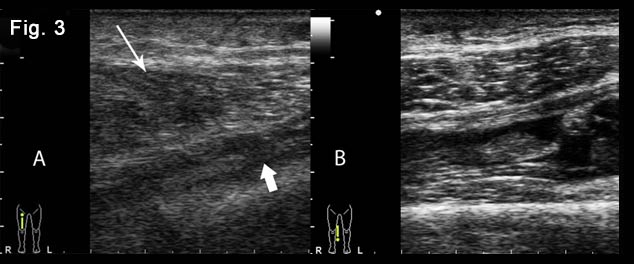

A. Grayscale sonography of the site of trauma revealed partial muscle disruption creating a defect which is filled with a hypoechoic haematoma (arrowhead). There was also an ill-defined hyperechoic area surrounding the muscle fiber disruption, corresponding to edema and hemorrhagic changes (arrow).

B. Power Doppler imaging shows blood flow signals around the injured area.